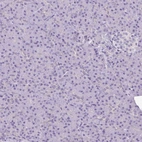

Immunohistochemistry analysis in human heart muscle and pancreas tissues using HPA019763 antibody. Corresponding MYL2 RNA-seq data are presented for the same tissues.